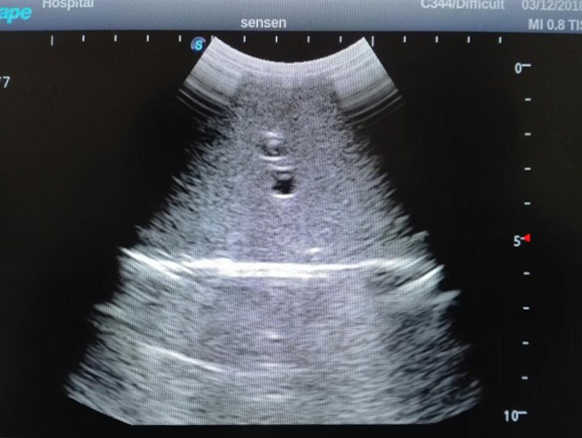

2) High quality ultrasound image with clear structures like gallbladder, liver, intestines, arteries and veins etc.

4) ltrasound gallbladder pathologies like cholecystitis, gallstone and polypoid degeneration